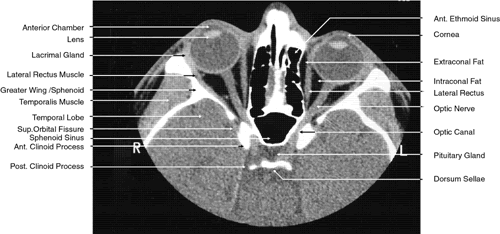

2D CT imaging is most frequently performed in the axial plane (Fig. 2). The bony anatomy of the orbit, optic canal, and intracranial cavity determines the exact orientation of this plane to provide the best visualization of both bone and soft tissue. The bony orbit is shaped like a quadrilateral pyramid lying on its side and with its base facing anteriorly. The medial orbital walls are almost parallel, although they tend to converge toward the midline in their posterior aspect. The lateral orbital walls diverge at approximately 45 degrees to the midline. The orbital axis is about 23 degrees divergent from the midline. The orbitomeatal line (Reid's baseline or the Frankfurt-Virchow line) is an important radiologic landmark for imaging the orbital structures. It is a line that extends from the upper margin of the external auditory meatus to the inferior orbital rim. The orbital floor is at approximately a -20-degree angle with this line, and the optic canal is at approximately a -30-degree angle with this line. Axial scans of the orbit are performed parallel to the orbitomeatal line, in contrast to axial scans of the intracranial contents, which are performed in a plane parallel to the orbital roof, which is at a + 30-degree angle to this line. The optic chiasm is also best imaged in a plane parallel to the orbitomeatal line. Although both the optic canal and nerve can be adequately visualized with axial scans parallel to this plane, scans of these structures are more precisely performed if the image plane is at a -30-degree angle to this line with the globe in upward gaze. This straightens the nerve and places its axis in the same plane as the canal. The optic canal of infants and young children is at approximately a -20-degree angle with the orbitomeatal line, and in these age groups the scanning angle is appropriately modified for precise imaging of this structure. For orbital scans a 3-mm slice thickness is usually employed; for scanning the optic nerve and canal, a 1.5-mm slice thickness is recommeded to image these structures completely (Fig. 3). Thin-slice technique is helpful in reducing the effects of partial volume averaging, thus improving image resolution of small-diameter structures such as the optic nerve. In contrast, axial scans of the intracranial contents are usually 5- or 10-mm thick slices, although thinner slices are often used when imaging structures such as the cavernous sinus, suprasellar cistern, pituitary gland, and optic chiasm. Generally, the radiation dose associated with thin-cut CT imaging is 30 mGy (using 3-mm slice increments) to 80 mGy (using consecutive 1.5-mm scans), which is considerably less than complex motion tomography of the facial area and similar to standard plane film head scans.

Fig. 2. Axial computed tomography scan at the level of midorbit.

Fig. 3. Axial computed tomography scan of the orbital apex and optic canal.

The globe is shown in Figure 12. The orbit and periorbital structures are shown in Figures 13 through 16, and the optic canal is shown in Figures 17 through 26. The cavernous sinus and optic chiasm are shown in Figures 27 and 28, and the posterior visual pathway and cranial nerves are shown in Figures 29 through 33.

Fig. 22. Axial images at the level of inferior orbit. A. Computed tomography scan. B. T1-weighted magnetic resonance imaging.

Fig. 23. Axial images at the level of midorbit. A. Computed tomography scan. B. T1-weighted magnetic resonance imaging.

Fig. 24. Axial images at the level of superior orbit. A. Computed tomography scan. B. T1-weighted magnetic resonance imaging.